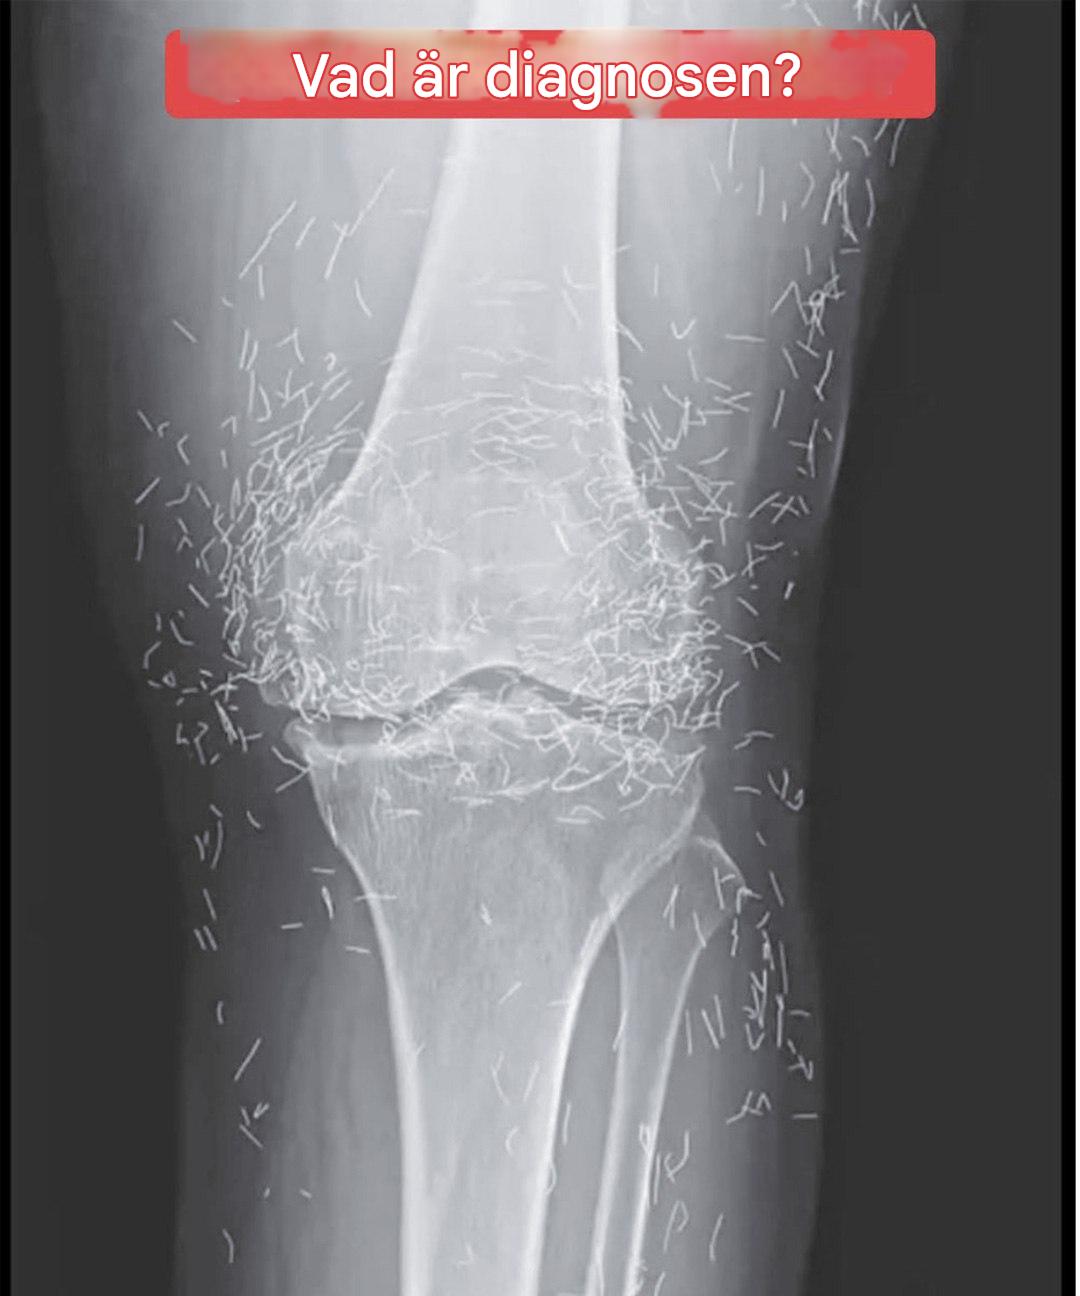

Na zdjęciu rentgenowskim kolan kobiety widać setki złotych igieł

Wyobraź sobie, że robisz sobie zdjęcie rentgenowskie z powodu bólu kolana... i odkrywasz, że twoje ciało kryje prawdziwy skarb! To właśnie przydarzyło się 65-letniej kobiecie, której zdjęcia medyczne ujawniły dość nieoczekiwaną obecność. To, co zobaczyli lekarze, wywołało o wiele więcej pytań niż dało odpowiedzi. Za tym intrygującym obrazem kryje się metoda, która wciąż jest stosunkowo nieznana we Francji, ale mimo to jest szeroko stosowana na całym świecie...

Podobnie jak wiele pracujących lub emerytowanych kobiet, ta pacjentka z Korei Południowej cierpiała na chorobę zwyrodnieniową stawów kolanowych. Ta choroba, często występująca u osób starszych, powoduje uporczywy ból, sztywność stawów i może poważnie ograniczać codzienne funkcjonowanie. Pomimo kilku konwencjonalnych metod leczenia – leków przeciwbólowych i przeciwzapalnych – ból nie ustępował, a dodatkowo dokuczały jej nieprzyjemne skutki uboczne ze strony układu pokarmowego.

W tym momencie sięgnęła po znaną w Azji alternatywę: akupunkturę. Ale nie byle jaką akupunkturę...